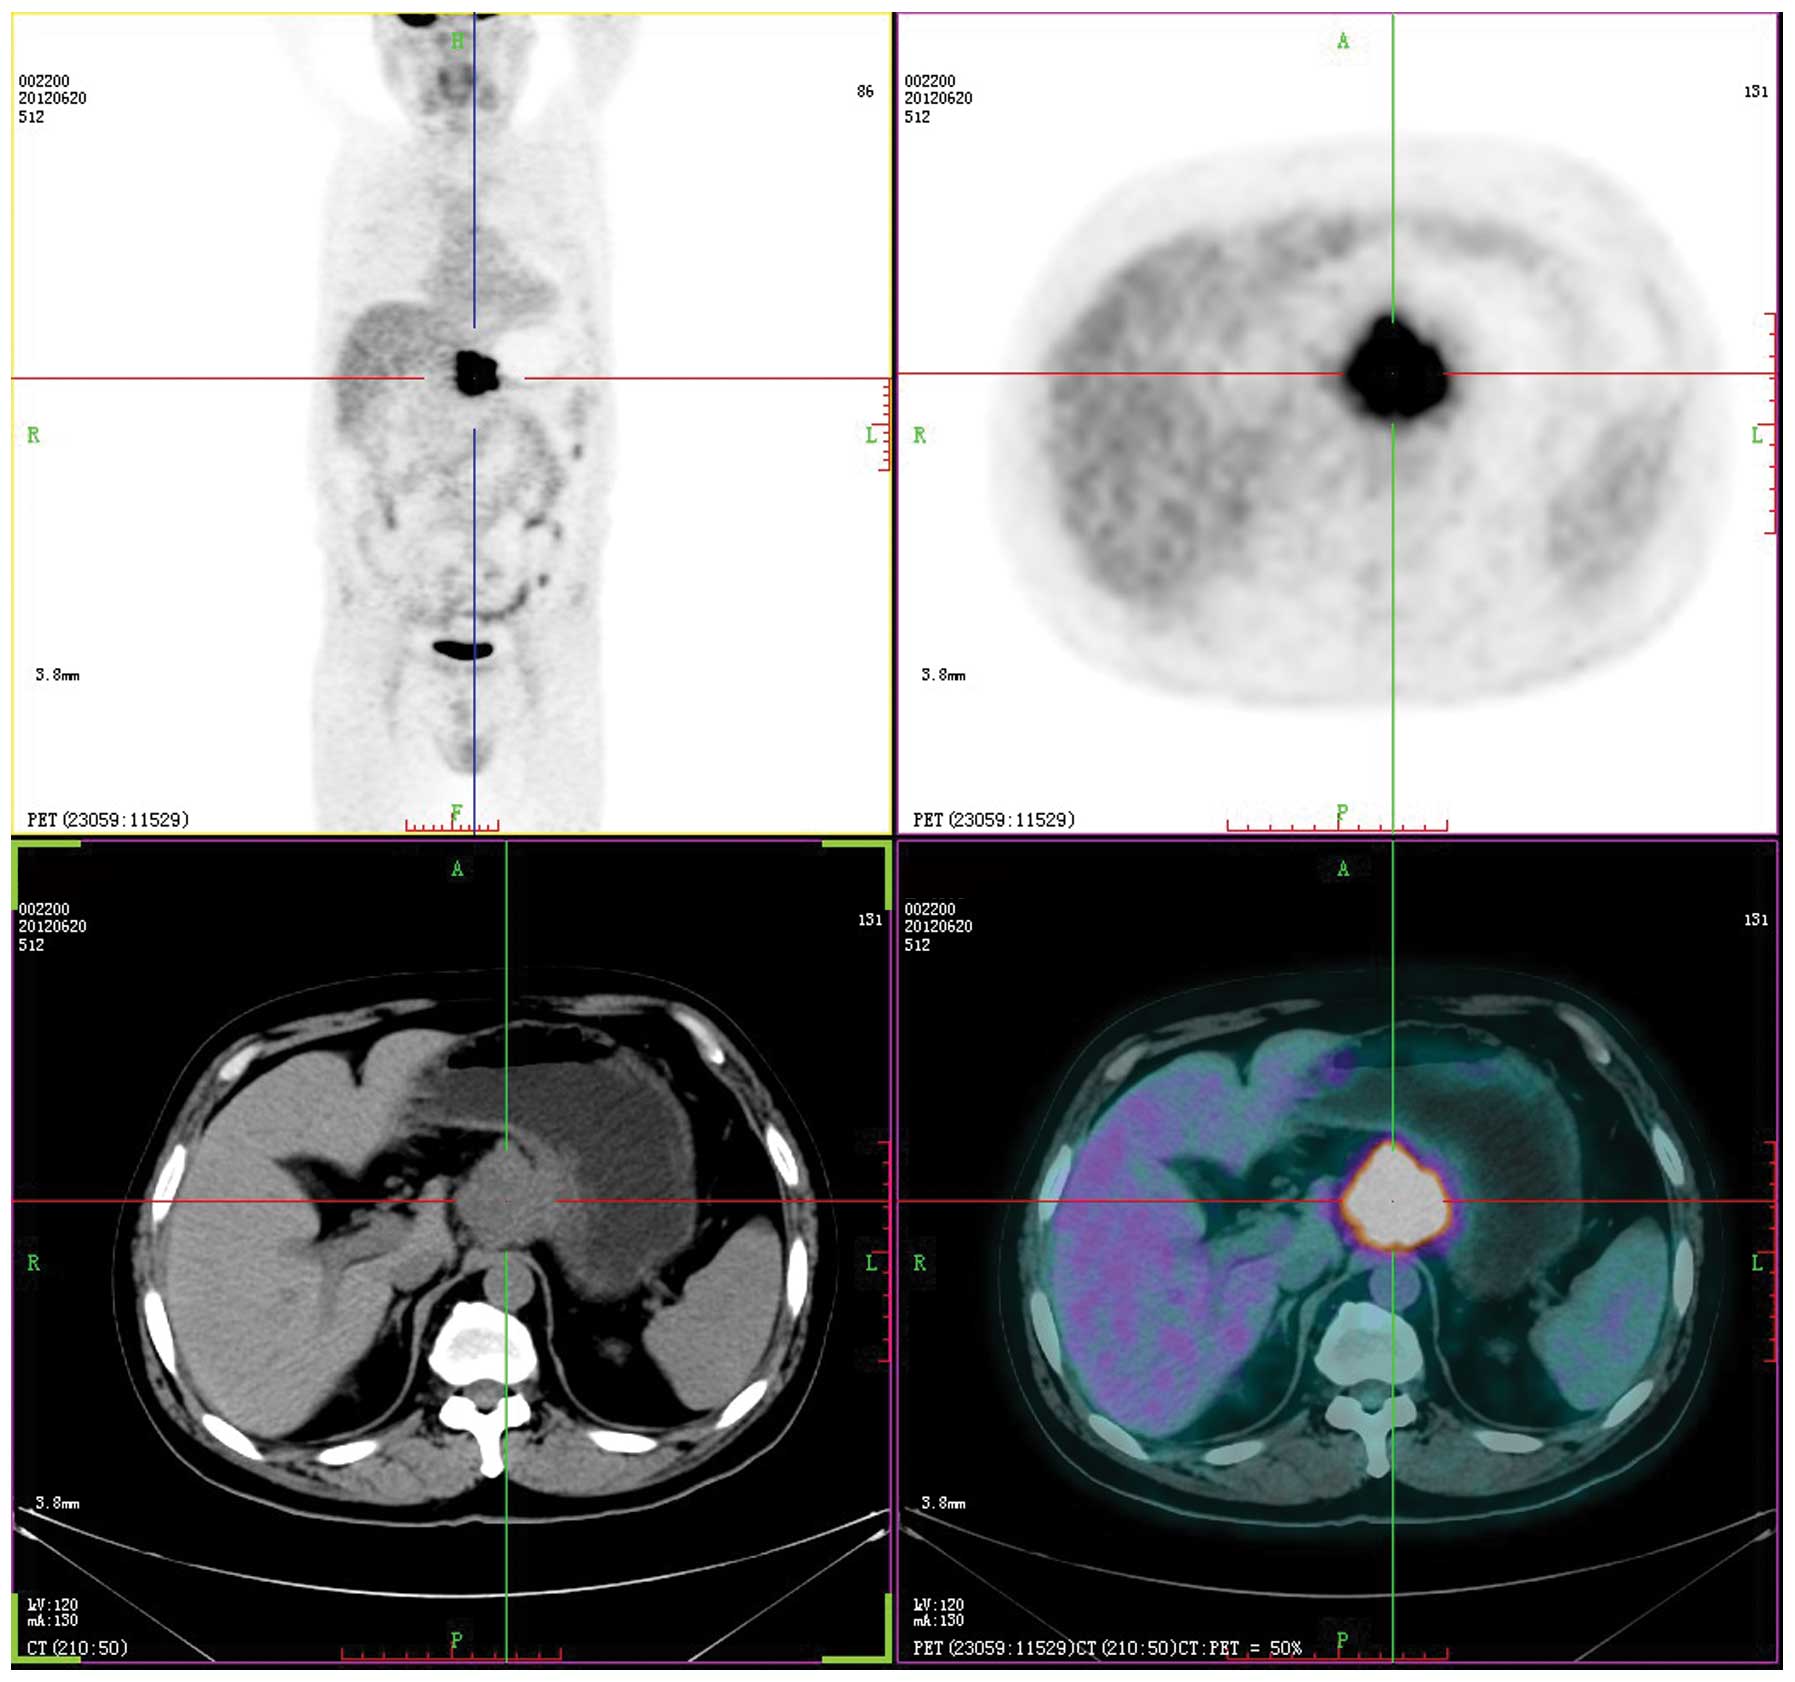

Laboratory studies revealed that the complete blood count and blood chemistry were within the normal range. No abnormal tumor markers were detected: Cancer antigen (CA)125, 3.15 KU/l (<35.00 KU/l); CA15-3, 2.16 KU/l (<35.00 KU/l); CA19-9, 3.57 KU/l (<35.00 KU/l); CA242, 2.58 KU/l (<20.00 KU/l); α-fetoprotein, 6.57 ng/ml (<20.00 ng/ml); carcinoembryonic antigen, 2.25 ng/ml (<5.00 ng/ml); neuron-specific enolase, <1.0 ng/ml (<13.00 ng/ml); ferritin, 19.70 ng/ml (male, <322.00 ng/ml; female, <219.00 ng/ml); human growth hormone, 2.20 ng/ml (<7.50 ng/ml); or β-human chorionic gonadotropin, <0.03 mIU/ml (<3.00 mIU/ml). Axial positron emission tomography (PET), computed tomography (CT), PET/CT and maximum intensity projection images are shown in Fig. 1. PET/CT identified a hypermetabolic lesion in the interspace between the liver and stomach. There was no additional fludeoxyglucose (18F) uptake, which indicated a primary site on the transaxial PET/CT scans of the head, neck, chest, pelvis, extremities or other abdominal organs (including the spleen, pancreas, gallbladder, kidney, large and small intestines). The patient subsequently underwent surgical resection. The tumor was located in the interspace between the liver and stomach, it measured 6×5 cm, was close to the left gastric artery, and invaded the gastric wall and the pancreas. Intraoperative fast pathological sections revealed that the tumor tissues were composed of nidulant, multi-mitotic cells and necrosis, which were identified as SCC (Fig. 2); therefore, the tumor was resected and a proximal gastrectomy was performed.

Figure 1

Positron emission tomography-computed tomography demonstrated a hypermetabolic lesion (standardized uptake value, 12.8) in the interspace between the liver and stomach. There was no additional fludeoxyglucose (18F) uptake, which indicated a primary site in other organs.